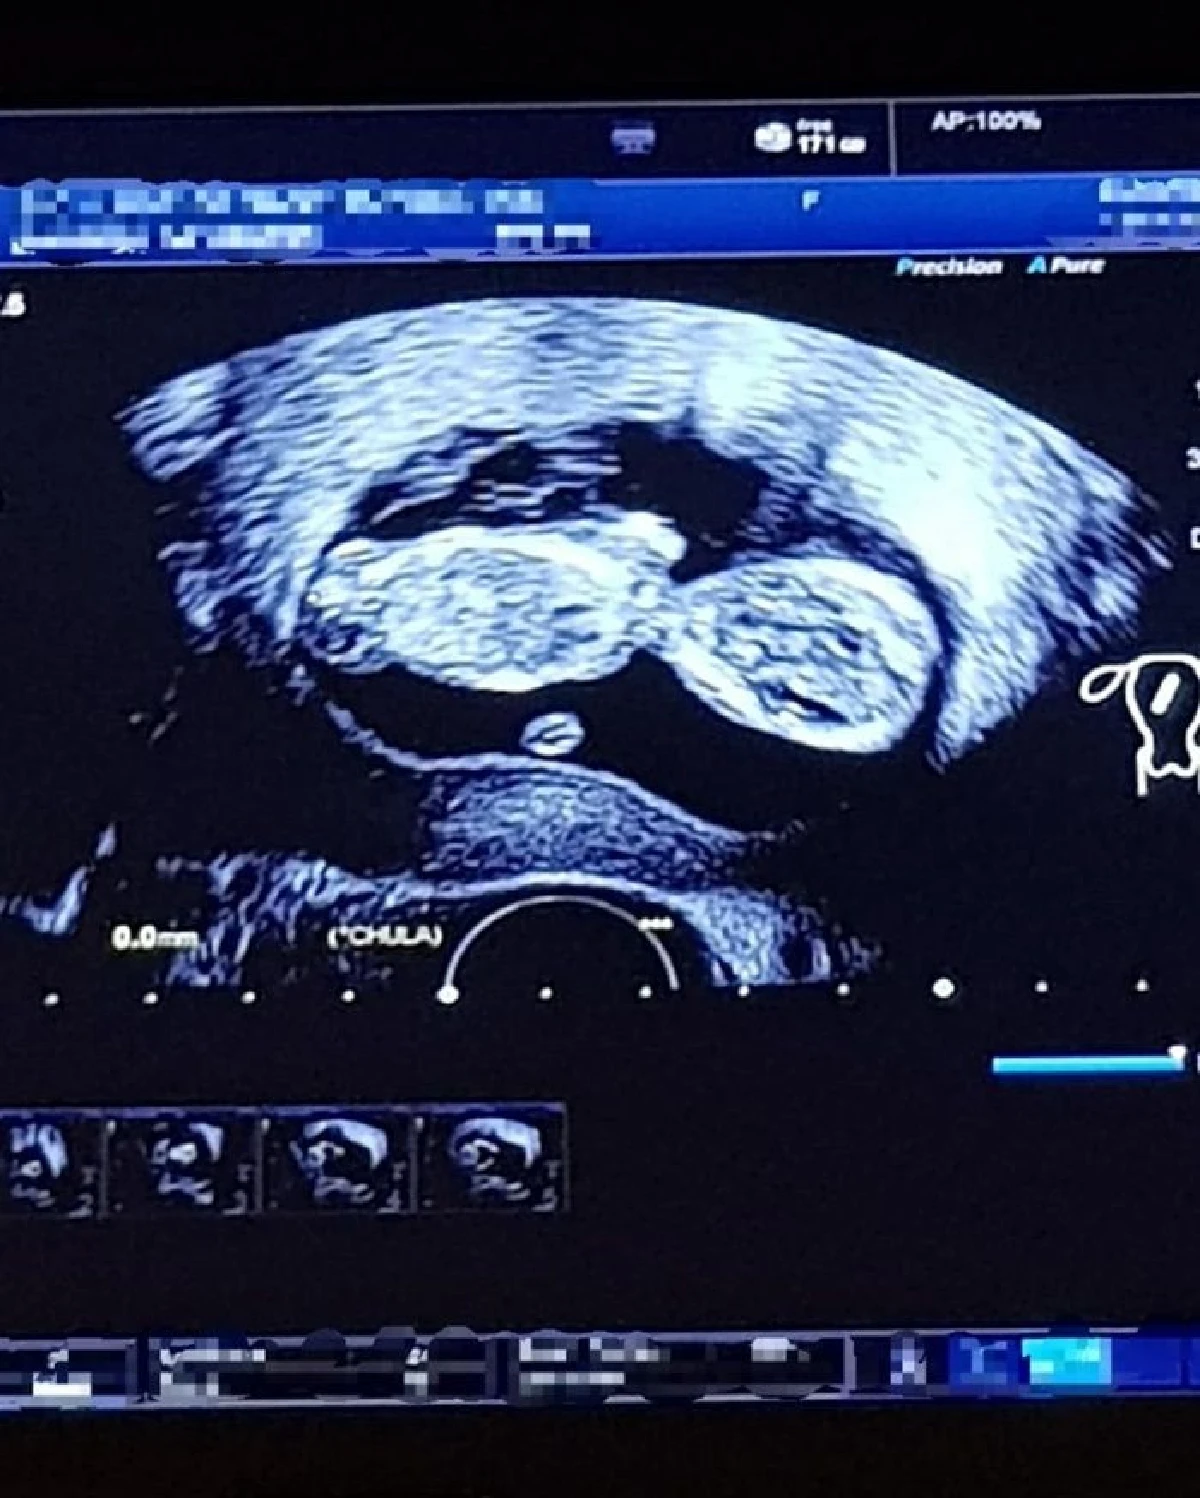

โดยสาว “แนนซี่” ได้เผยภาพถ่ายอัลตราซาวด์ลูกน้อยลง IG พร้อมข้อความว่า "When you just can’t hide it anymore and now it’s completed the first trimester. Can’t wait to see u my baby #ต่อไปนี้ไม่ทักกันว่าอ้วนขึ้นแล้วนะคะ #12weekspregnant”